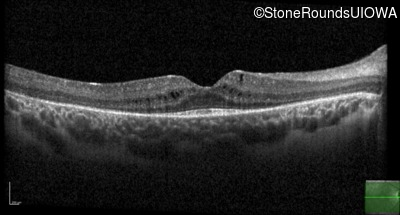

Age at visit: 8 years